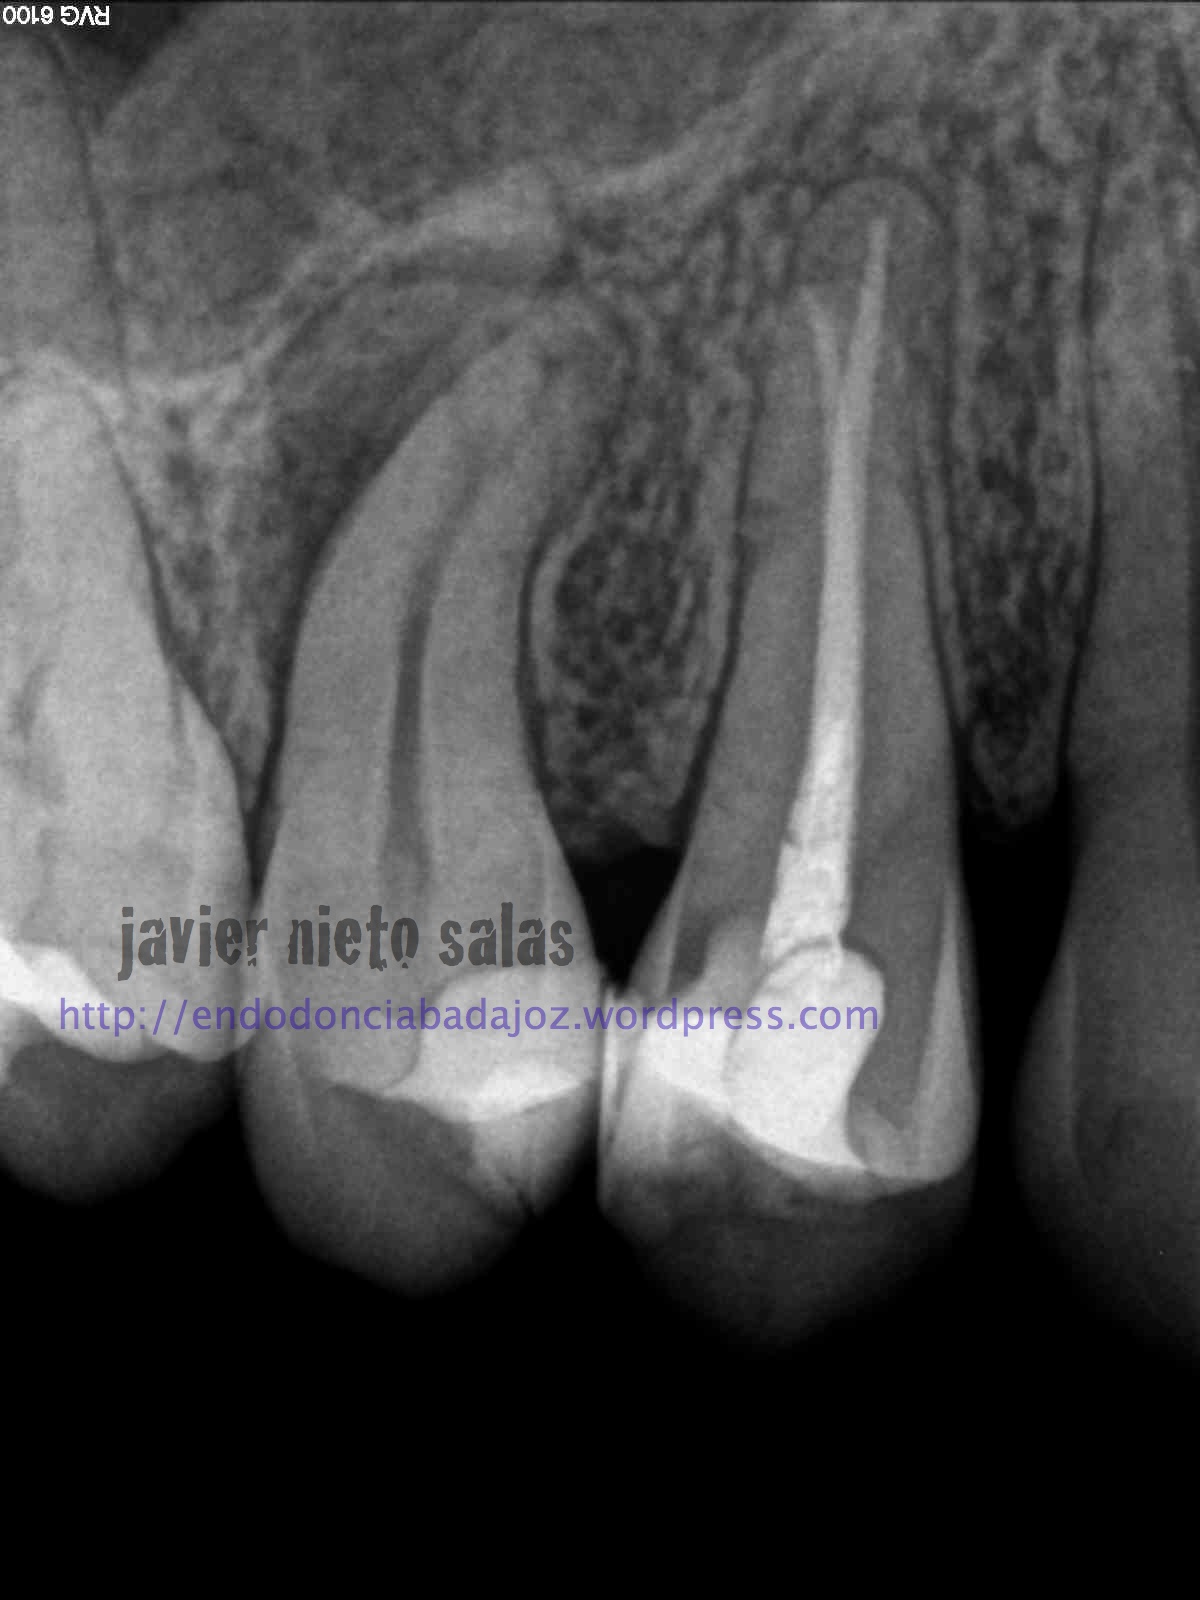

En el  primer caso de hoy, podemos ver la importancia de pararse a ver la radiografía inicial, el tamaño de la lesión y el posible origen, algo, a mi parecer, bastante importante.

Así pues, en esta primera imagen vemos la lesión lateral que nos hace sospechar de una posible salida a ese nivel. Modificando nuestra técnica de limpieza y obturación: